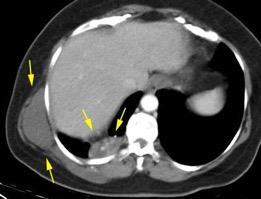

Masa axilar izquierda y derrame pleural derecho. Implantes pleurales, paraespinales . Ganglios en mamaria interna. Linfoma B difuso

Linfoma NH de cél. B. Invasión Transtorácica.

Afectación axilar